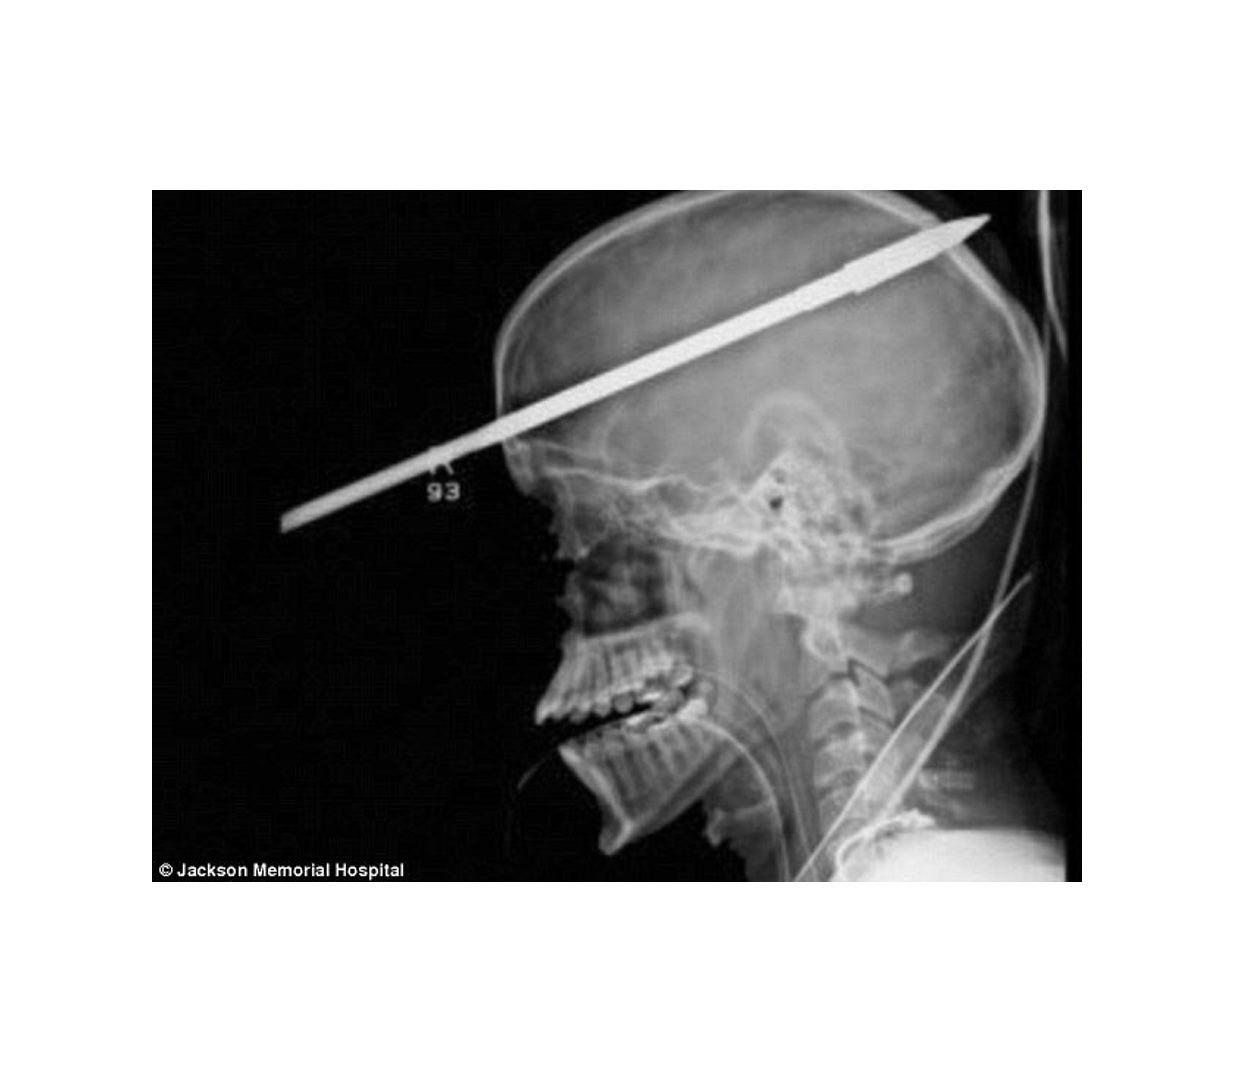

Even if it's just meant for fish, spearguns are designed to kill. Speargun safety is one of the most fundamental aspects of preventing spearfishing tragedies outside of blackouts. New divers always think that their greatest risks are from sharks or other environmental issues, but the reality is your greatest risks come from blackouts and loaded spearguns. Every few months there seems to be a diver that is shot with their own or another divers speargun. There are a couple rules you can impose on yourself that will prevent any problems with this.